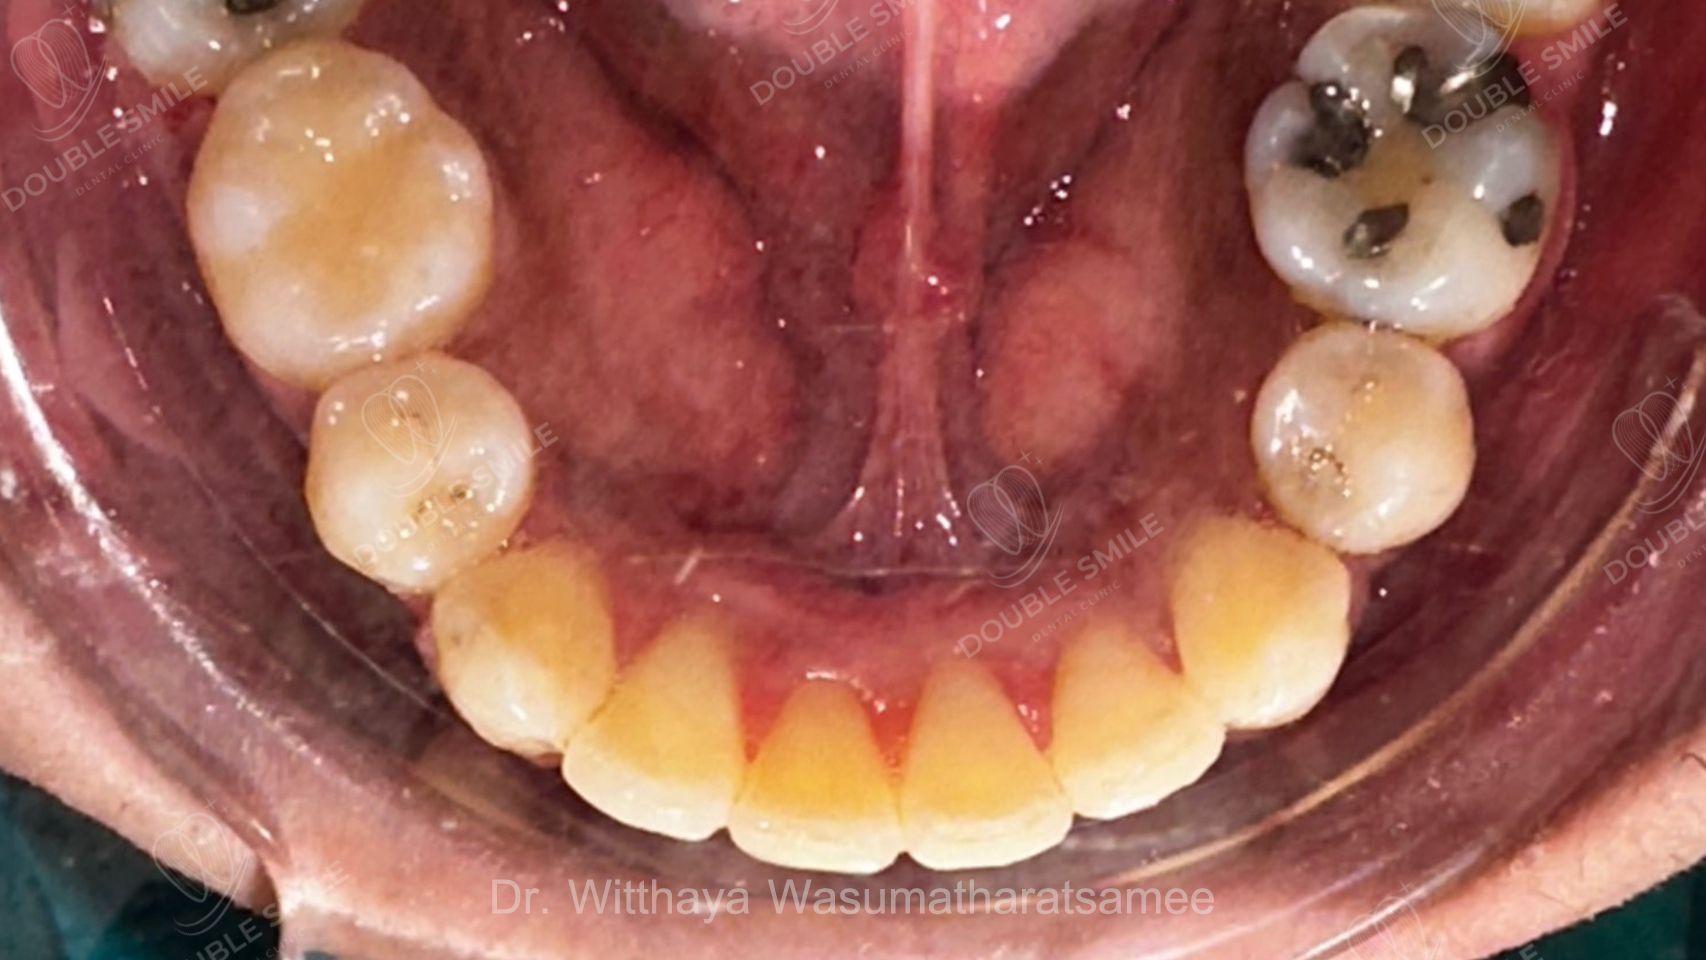

เคสรีวิวที่ 55

Before

Case Review

Before & After